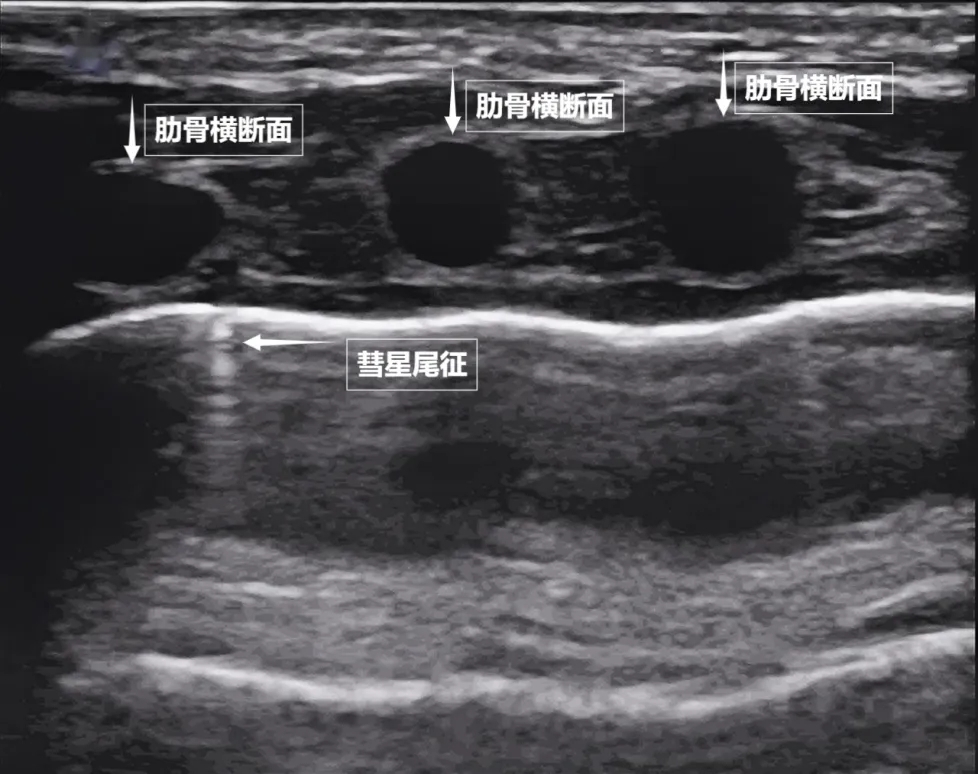

第二景:“沙滩与浪花”——肺滑动征

如果我们把超声图像调成实时动态模式,把“照片”变成“电影”,更神奇的一幕出现了。随着呼吸,胸膜线会随胸廓运动轻柔滑动,这就是“肺滑动征”。它意味着肺与胸壁正紧密相依、自由顺畅地呼吸。若肺与胸壁间有气胸或胸腔积液,这种滑动会消失。有时,在胸膜线下方还会出现细小的亮白色闪烁点,称为“彗星尾征”(见下图)。其少量、孤立出现时,通常是正常肺小叶间隔的反射,无需担心。

图为正常新生儿肺部超声表现。